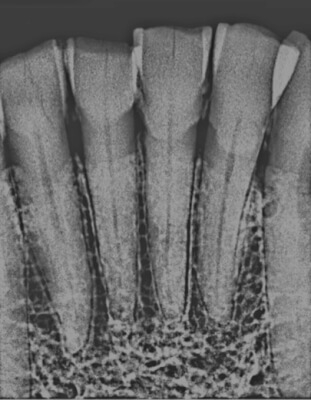

• Using an X-ray is part of the research technique.

Photo Credit: Courtesy of Gwyn Madden

Examining pulp chambers -- which fill in as people get older -- is promising for better determining an age on a skeleton because that area of the tooth is more protected than enamel, Madden said. With enamel studies, researchers could only determine an age range for skulls up to about middle age; with pulp chamber studies, they are able to pinpoint age groups in a range up to the 60s with a diminished error rate.

Madden and Piechocki X-rayed the teeth, used pixels to measure the filling in the pulp chamber and then used an equation to produce their findings.